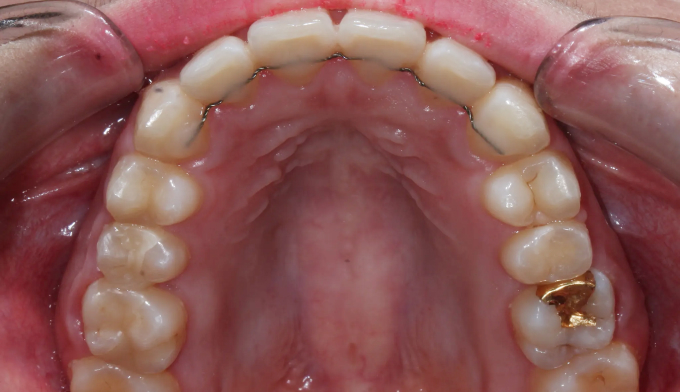

돌출입과 불규칙한 앞니를 가지고 있습니다. 그리고 아래쪽에 ‘임플란트’가 있습니다.

돌출입을 해소하고 앞니를 가지런하게 만들기 위한 공간을 만드는 과정중에는 저 임플란트를 꼭 제거해야 했으나, 최대한 발치 없이 교정을 진행하였습니다.

후방이동이 불가하므로 악궁확장을 통하여 공간확보를 시도하였고, 동시에 돌출감도 해소되었습니다.

최종적으로 임플란트의 존재때문에 중심선을 맞추지는 못했으나 환자분은 너무 만족해하셨습니다.